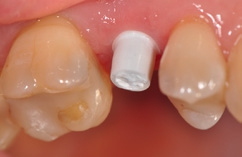

Für den Reentry wurde für das Einbringen des Gingivaformers eine minimale krestale Inzision angelegt (Abb. 13). Nach Abheilung der Weichgewebe (Abb. 14) konnte 2 Wochen später mit Reposition des Abformpfostens geschlossen abgeformt (Abb. 15) und das Meistermodel erstellt werden Da es sich um ein 2-teiliges Implantatsystem handelt und die Abutments ebenfalls aus hochfester ATZ-Keramik bestehen, lassen sich diese – falls nötig – entweder in der Praxis oder im Dentallabor durch Beschleifen individualisieren (Abb. 16). Für NobelPearl stehen sowohl gerade als auch 15° abgewinkelte Abutments mit 1 mm und 3 mm Gingivahöhe zu Verfügung. Im CAD/CAMVerfahren wurde eine monolithische Zirkonkrone aus Zolid FX (Amman Girrbach) mit okklusalem Zugang zum Schraubenkanal gefertigt (Dentallabor Studio für Zahntechnik, Dirk Tartsch).

Verklebung der Krone

Nach der Einprobe von Abutment und Krone (Abb. 18 und 19) erfolgt ihre Verklebung analog einer Titanklebebasis entweder extraoral im Dentallabor oder, wie in diesem Fall, intraoral. Der Vorteil des Verklebens im Patientenmund liegt darin, dass eventuell auftretende Spannungen zwischen Abutment und Implantat abgefangen werden können. Solche Spannungen können bereits durch nicht ganz korrekte Reposition des Abformpfostens bei einer geschlossenen Abdrucknahme ausgelöst werden, durch kleine Ungenauigkeiten bei der Gestaltung der Kontaktpunkte oder aber auch durch das – wie bei jedem Implantatsystem mehr oder weniger vorhandene – „Spiel“ zwischen Implantat, Abformpfosten, Laborimplantat und Abutment. Dabei kann Titan als elastisches Metall solche „Mikrospannungen“ eher ausgleichen als die harte, nicht elastische Keramik.